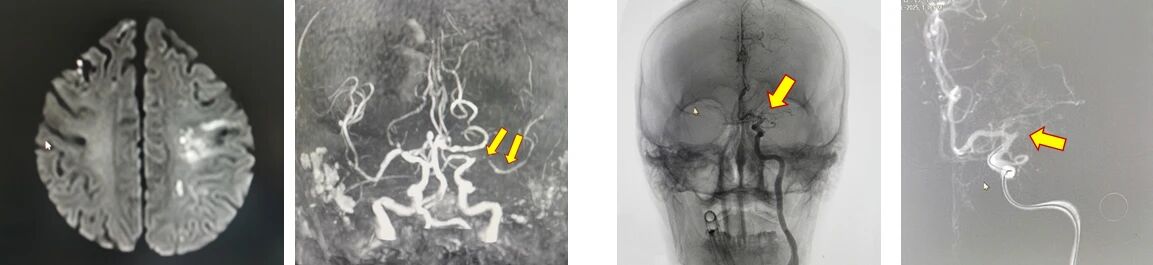

影像科磁共振检查很快锁定「元凶」——左侧大脑中动脉重度狭窄导致的左侧脑梗塞,此时,患者的 NIHSS(美国国立卫生研究院卒中量表)评分已高达 17 分。

脑卒中发病急、进展快,就在完成各种检查后几分钟,老人的病情又进一步加重——从仅有的言语障碍、右侧肢体无力,迅速发展为右侧肢体完全瘫痪,意识障碍也明显加重。原本 MRA 显示的是左侧大脑中动脉重度狭窄,而在 DSA 检查时发现,该处血管已经完全不显影,患者大脑供血完全中断,取栓治疗刻不容缓。

当日 13 时许,取栓操作正式开始。尽管首次穿刺至血管开通仅用 10 分钟左右,但挑战接踵而至——由于患者的血管内病变为斑块和血栓的复合病变,虽经过取栓后即刻血流恢复良好,但数分钟后再次出现血流不畅。

面对这块「硬骨头」,天佑医院神经介入团队果断调整策略,选择一枚药物球囊扩张支架,稳妥穿过迂曲的血管路径,最终成功置入病变最狭窄处,球囊扩张,支架释放,血流终于得以稳定重建。观察 30 分钟,血流通畅稳定,手术成功。